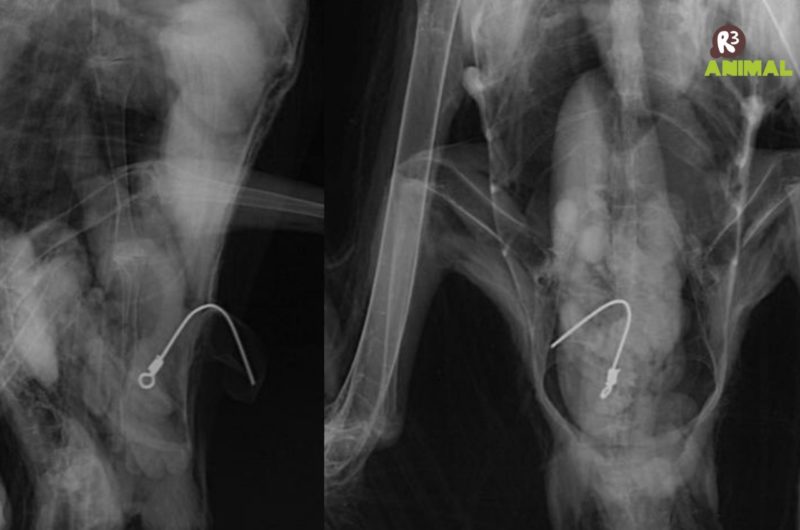

Uma fragata resgatada por um navio pesqueiro no dia 26 de maio e encaminhado para a R3 Animal, em Penha, foi submetida a uma cirurgia para a retirada de uma haste metálica de 10 cm alojada no estômago na última quarta-feira (9).

O objeto, um encastoador de pesca, usado em anzóis, perfurou a pele do animal e estava projetado para fora do corpo. Segundo a equipe veterinária, o animal está bem e em observação em Florianópolis.

Antes do procedimento, a ave foi anestesiada e passou por uma endoscopia para ajudar no planejamento da extração da haste. De acordo com a avaliação prévia da veterinária Janaina Rocha Lorenço, o objeto estava dentro da cavidade gástrica, com uma ampla área contaminada.

Ave passou seis dias em processo de estabilização. O exame radiográfico constatou que a haste metálica, de aproximadamente 10 centímetros, tratava-se de um apetrecho de pesca chamado de “encastoador”, um empate para anzol, utilizado para evitar o rompimento de linhas de pesca. Naquele momento, parte da haste que estava para fora da ave foi cortada para prevenir lesões. – Foto: Nilson Coelho/R3 Animal